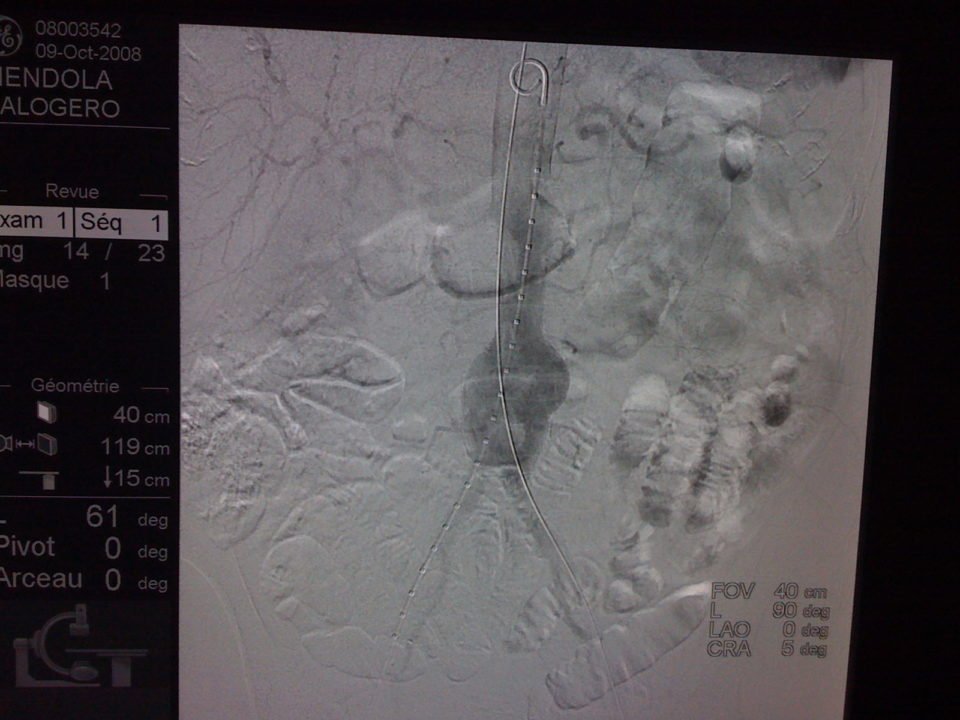

L’angioscanner aorto-iliaque est plus invasif mais plus reproductible que l’échographie et moins opérateur dépendant. C’est l’examen de choix avant un traitement par endoprothèse ou par chirurgie classique. Il permet les mesures exactes (« sizing ») de l’anatomie de l’anévrysme, de l’aorte et des artères iliaques avant mise en place d’une endoprothèse. Il permet la recherche d’autres anévrysmes au niveau fémoro-poplités et d’étudier l’ensemble de l’aorte.

Il existe deux types de traitement qui sont détaillés sur ce site, le traitement chirurgical classique et le traitement mini-invasif par endoprothèse. Le traitement mini invasif par endoprothèse est de plus en plus utilisé, on estime qu’il est utilisé dans 70% à 80% des cas.